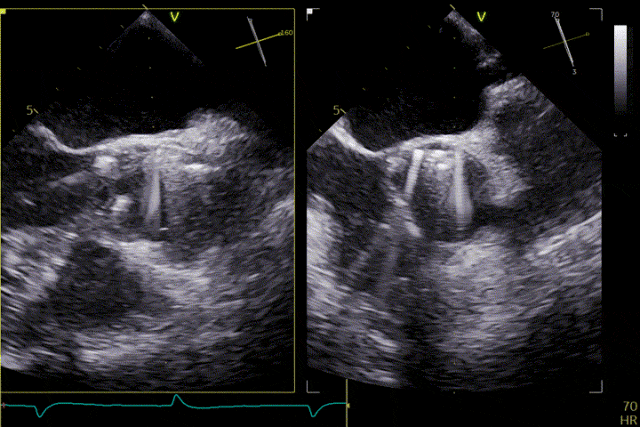

術前超聲

患者主動脈瓣重度反流得到糾正,術後無反流、無瓣周漏。術後心臟超聲顯示人工生物瓣啟閉功能良好,平均跨瓣壓差2 mmHg,血流速度正常。患者恢復情況良好,心功能較術前明顯改善。